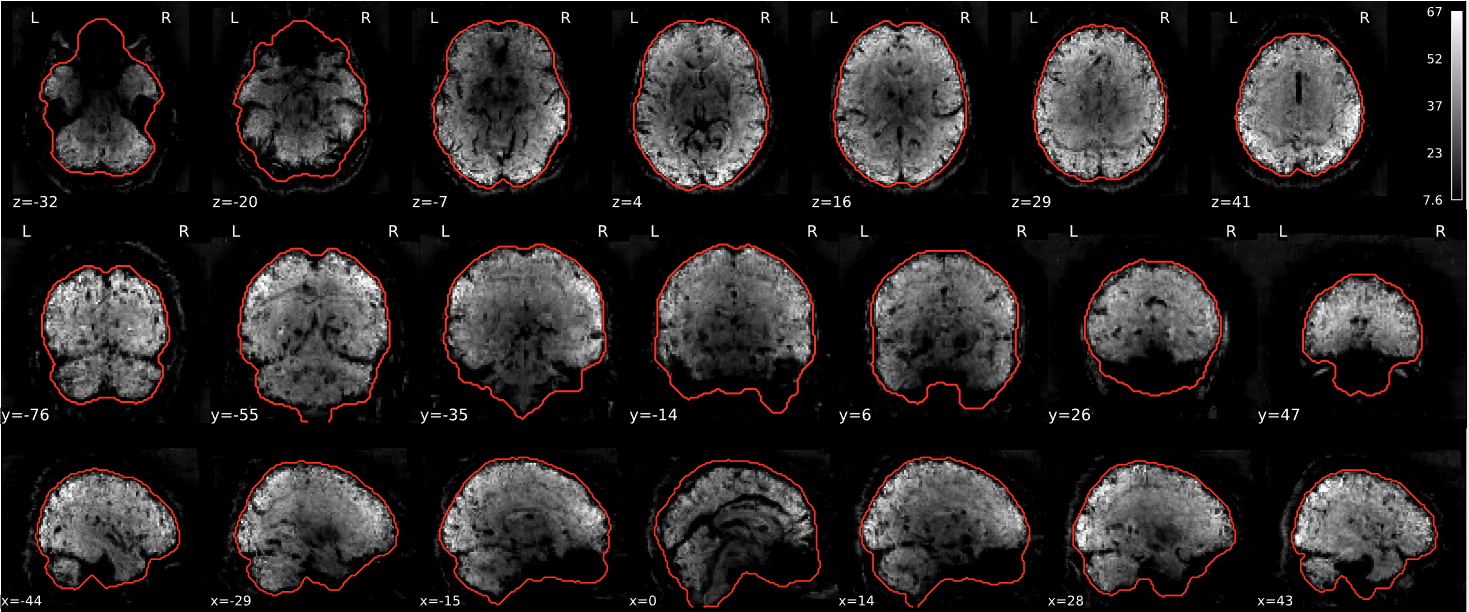

dT1w spatial normalisation

This QC step shows the registration of the T1 image to MNI space.

The registered T1 image is shown in the background with a brain atlas in MNI space as an overlay.

Example of a good subject

- If the registration performed well, you should see an overlap (i.e., correspondence of structures) between the MNI template and the T1 registered to the MNI space.

Example of a bad subject

- In case of poor registration, you should see a misalignment between the MNI template and the T1 (e.g., brain shifted down).

Summary

| good | bad |

|---|---|

| Structures of the MNI template and the registered T1 are well aligned | Structures of the MNI template and the registered T1 aren’t well aligned, e.g. brain is shifted downwards |